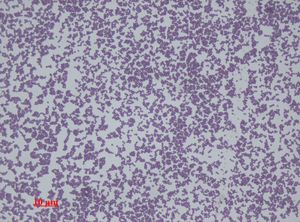

표피포도상구균(''Staphylococcus epidermidis'')은 그람 양성 구균으로, 포도송이 모양의 집단을 이루는 통성 혐기성 세균이다. 카탈레이스 양성,[35] 응고효소 음성이며, 호기성 호흡 또는 발효를 통해 생장할 수 있다. 일부 균주는 발효하지 않을 수 있다.[29][36]

표피포도상구균은 운동성이 없는 그람 양성 구균으로, 포도 모양의 군집을 이룬다.[31] 융기되어 있고 응집력 있는 흰색 집락을 형성하며, 하룻밤 배양 후 직경 1-2mm의 집락을 이룬다. 혈액한천배지에서 용혈되지 않는다.[31] 호기성 호흡이나 발효를 통해 자랄 수 있는 통성 혐기성이며 카탈레이스 양성,[35] 응고효소 음성이다.[29][36]

표피포도상구균은 운동성이 없는 그람 양성 구균으로, 포도 모양의 군집을 이루며 배열되어 있는 매우 강인한 미생물이다. 융기되어 있고 응집력 있는 흰색 집락을 형성하며, 하룻밤 배양 후 직경 1-2mm의 집락을 이루고 혈액한천배지에서 용혈되지 않는다.[31] 호기성 호흡이나 발효 양쪽 모두에 의해 자랄 수 있는 통성 혐기성이며 카탈레이스 양성,[35] 응고효소 음성이다.[29][36] 일부 균주는 발효를 하지 못할 수 있다.

표피포도상구균(''Staphylococcus epidermidis'')은 운동성이 없는 그람 양성의 구균으로, 포도송이 모양으로 군집을 이루는 매우 강인한 미생물이다. 혈액한천배지에서 하룻밤 배양하면 직경 1~2mm 정도의 융기된 흰색 집락을 형성하며, 용혈은 일어나지 않는다.[31] 호기성 호흡이나 발효를 모두 할 수 있는 통성 혐기성이며, 카탈레이스 양성,[35] 응고효소 음성이다.[29][36]